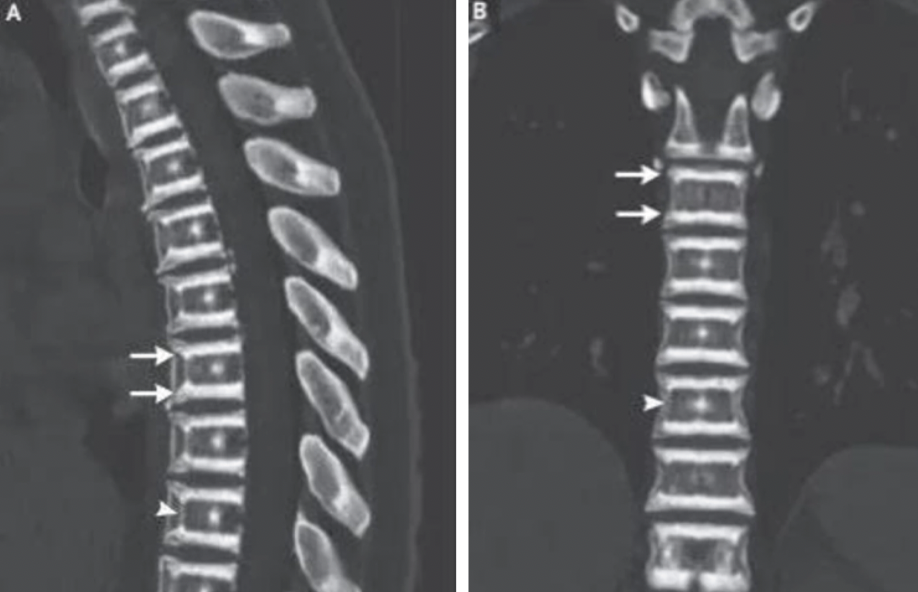

A woman who suffered from back pain for two months had shocking X-ray results. Credit: The New England Journal of Medicine.

According to a report from The Sun, a woman in her late thirties had been experiencing back discomfort and only decided to seek medical attention after two months. Even though she has a history of osteoporosis in her family, it was unclear why she waited such a long time to get the help she needed.

The woman was given a thorough physical examination, and at first, the doctors didn't find anything out of the ordinary. But when they took a number of X-rays, they discovered that she had a medical condition called 'sandwich vertebrae'.

This is a condition in which the thoracic spine has sclerotic bands—this means that the bones have reacted badly to the growing process. Doctors also noticed that she had developed a 'bone inside a bone' as a result of this condition.

'Osteoclasts in patients with this condition are unable to resorb bone, which causes bone density to increase, primarily in the spine, the pelvis, and the base of the skull,' said the medical experts at the University Minho School of Medicine.

'The radiographic findings of sandwich vertebrae and bone within bone strongly suggest the diagnosis and should prompt genetic testing.'

A woman who suffered from back pain for two months had shocking X-ray results. Credit: The New England Journal of Medicine.

According to a report from The Sun, a woman in her late thirties had been experiencing back discomfort and only decided to seek medical attention after two months. Even though she has a history of osteoporosis in her family, it was unclear why she waited such a long time to get the help she needed.

The woman was given a thorough physical examination, and at first, the doctors didn't find anything out of the ordinary. But when they took a number of X-rays, they discovered that she had a medical condition called 'sandwich vertebrae'.

This is a condition in which the thoracic spine has sclerotic bands—this means that the bones have reacted badly to the growing process. Doctors also noticed that she had developed a 'bone inside a bone' as a result of this condition.

'Osteoclasts in patients with this condition are unable to resorb bone, which causes bone density to increase, primarily in the spine, the pelvis, and the base of the skull,' said the medical experts at the University Minho School of Medicine.

'The radiographic findings of sandwich vertebrae and bone within bone strongly suggest the diagnosis and should prompt genetic testing.'